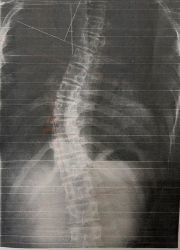

レントゲンのビフォーアフター)

写真1(施術前) 写真2(5か月後)

○コブ角上27度⇒25度(2度改善)、下40度⇒33度(7度改善)

※コブ角は専門医の診断

施術19回:コブ角33度

施術前:コブ角40度